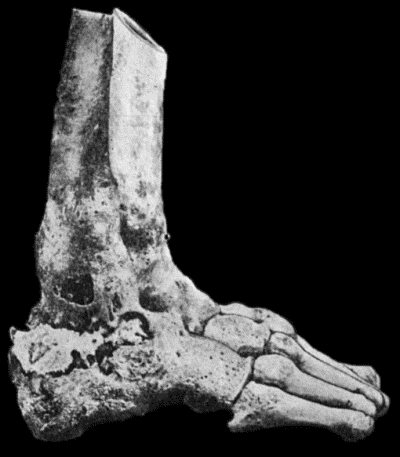

| 165. | Charcot's Disease of both Ankles: back view | 536 |